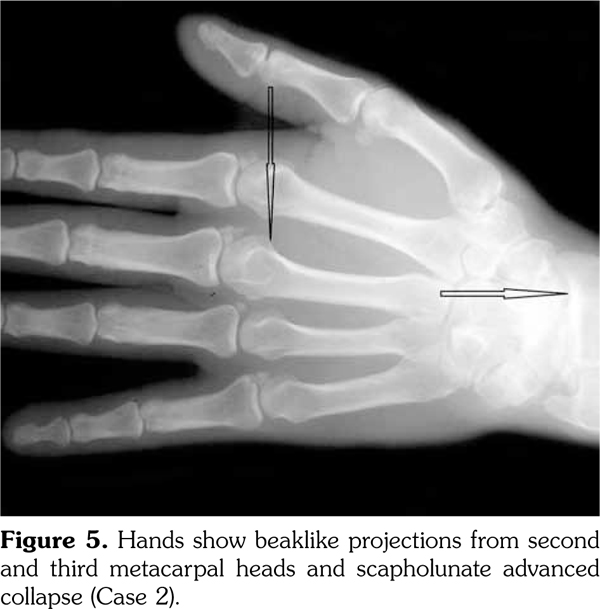

On examination, there was swelling and painful restriction of movement in her right knee. Imaging revealed calcification of cartilage of wrists, knee joints and hip joints although no microscopic confirmation was possible at this stage (Figure 1-4). She was investigated for a possible cause for CC, although investigations to screen for a metabolic cause turned out to be negative with a possibility for hereditary CC.

Case 2- A 39-year-old male patient presented with swelling of both knee joints. He also gave a history of recurrent painful swelling of knee joints and wrist joints for more than 10 years and was treated by an Ayurvedic physician. Other medical history or family history of medical problems were insignificant. There was a massive swelling of both knee joints with effusions, which was aspirated and the X-rays revealed calcification of the articular cartilages (Figure 5). A written informed consent was obtained from the patient.

His hand X-rays showed hook like projections arising from radial aspect of second and third metacarpal heads with scapholunate advanced collapse and indentation of distal radius by the scaphoid bone. It also showed CC of the triangular fibrocartilage (Figure 6).